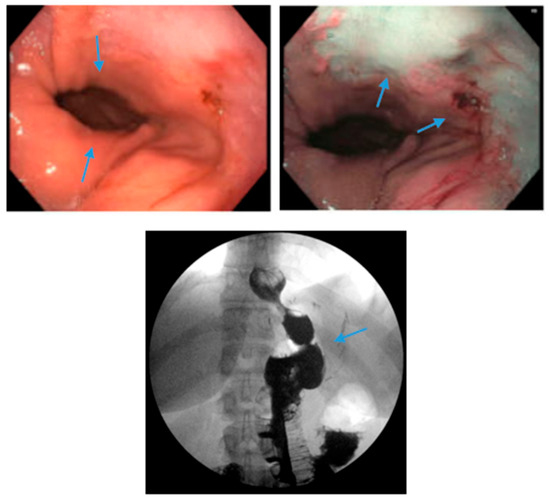

Figure 5.

Upper endoscopy demonstrates Los Angeles Grade C esophagitis in a patient following sleeve gastrectomy (arrows, left). A Bravo™ capsule was placed endoscopically for pH monitoring (Medtronic, Minneapolis, Minnesota, USA) (arrow, right).

Figure 6.

Endoscopic images reveal a 3 cm hiatal hernia (arrows, top left) and Los Angeles Grade B esophagitis (arrows, top right) in the lower third of the esophagus with narrow-band imaging in a patient post-sleeve gastrectomy with symptoms of gastroesophageal reflux disease. The patient eventually required Roux-en-Y gastric bypass (arrow, bottom) and concomitant hiatal hernia repair, as demonstrated on upper gastrointestinal series.